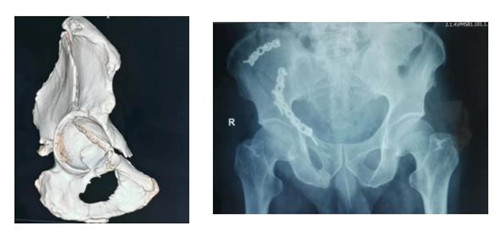

接诊该病人后胡洪波副主任前往CT室对骨折移位情况进行分析、定位。经过详细询问病史、查体,结合检查结果,骨三科团队确定采用经腹旁外侧入路为患者进行手术。手术耗时短,出血少,骨折复位满意,固定可靠,患者和家属对治疗效果十分满意。

骨盆髋臼骨折腹旁外侧入路也是胡洪波副主任在骨盆髋臼骨折领域继stoppa入路之后带来了第二个新的手术入路。腹旁外侧入路是进行髋臼前柱骨折的新的手术入路方式,此入路临近血管、神经、腹膜等重要器管,所以临床中还未能广泛开展。但因为此入路具有切口小、创伤少、患者恢复快等巨大优点,近年来已逐渐应用于临床,为骨盆髋臼骨折患者的快速康复带来了福音。